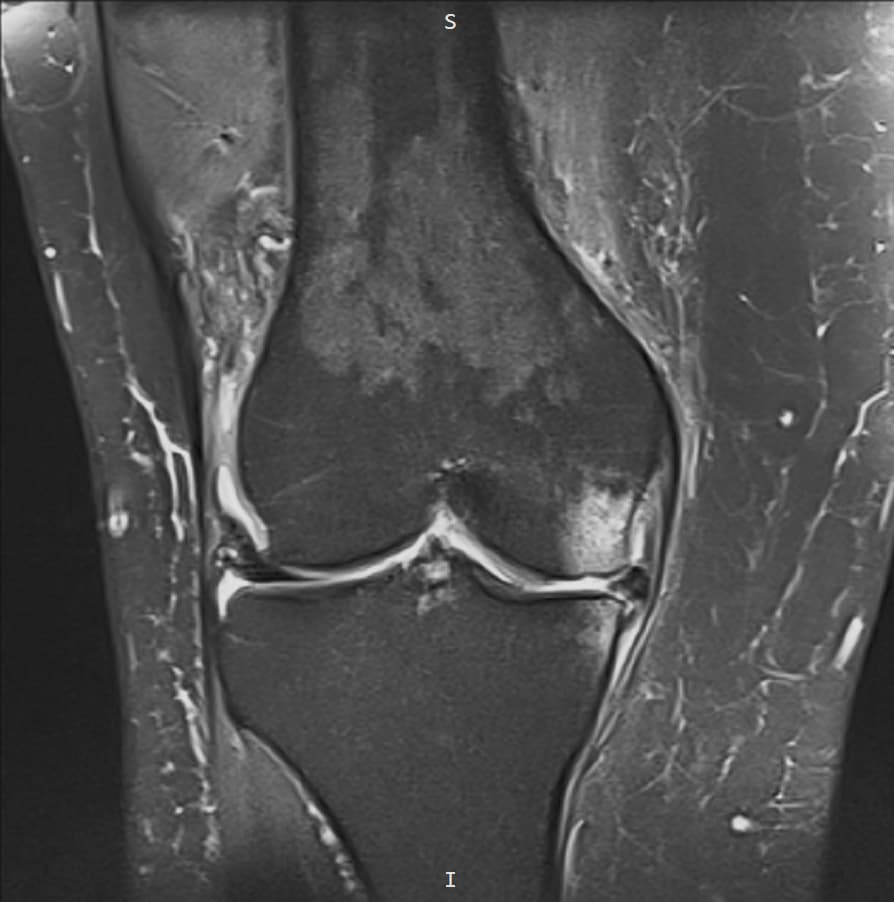

- RMN-ul genunchiului

RMN-ul este investigația cea mai utilă pentru evaluarea cartilajului articular.

RMN-ul este investigația cea mai utilă pentru evaluarea cartilajului și pentru identificarea leziunilor asociate ale genunchiului.